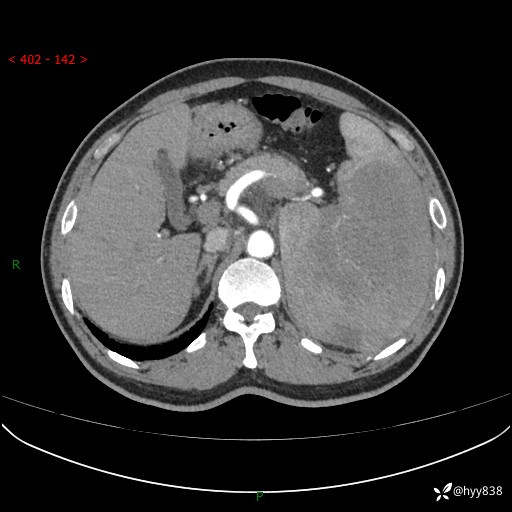

上腹部CT平扫

增强(动脉期+静脉期)